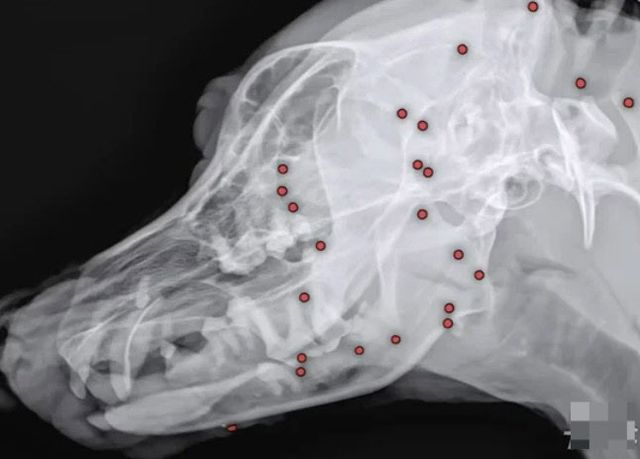

25일 VIP동물의료센터 측에 따르면 최근 도그어스플래닛에서 구조 후 해외 입양을 준비하던 백구 한 마리에 대한 건강검진을 했다가 충격적인 결과를 보게 됐다. 백구의 몸에 70개가 넘는 산탄총 파편이 박혀 있던 것이다.

구조 당시 겉으로 보기에 드러나지 않던 산탄총 총알들은 원인을 알 수 없는 이유로 백구 온 몸에 박혀 있었고, 동물병원에선 엑스레이, CT(컴퓨터단층촬영) 등 정밀검사에 들어갔다.

안승엽 VIP동물의료센터 원장은 “총알이 머리 쪽부터 어깨, 가슴통, 엉덩이, 다리까지 너무 많이 있었다”며 “살아있는 게 기적”이라고 밝혔다.

산탄총 파편 제거 수술은 총 3시간 동안 진행됐다. 맨눈으로 탄알을 다 확인할 수 없어서 투시기를 이용해 일일이 수술해야 했다고.

안 원장은 “탄알을 한 번에 다 제거하기는 현실적으로 어려워 백구의 얼굴을 위주로 최대한 많이 제거하는 방향을 선택했다”며 총 26개의 파편을 제거했다고 밝혔다.